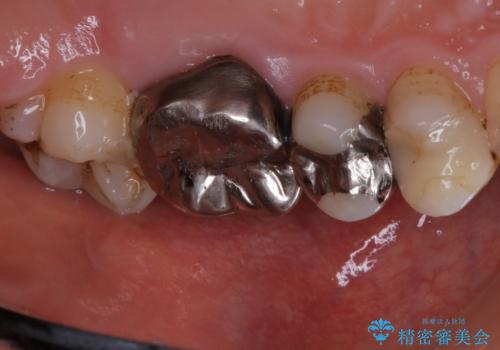

歯の表面に、茶色く色が残っている所がありますが、これは詰め物の変色の所と、虫歯になっている所です。以前に、CR(コンポジットレジン)による虫歯治療がされています。

CRは経年的劣化や、着色してしまうことがあります。PMTCでクリーニングを行うと、古いCRが目立つことがあるため、気になる際は詰め替えを行います。

茶色くなっている部分が、着色なのか、劣化なのか、虫歯によるものなのかは判別が難しいことがあります。そのため、定期的にPMTCを行うことで状態の確認が的確に行えます。